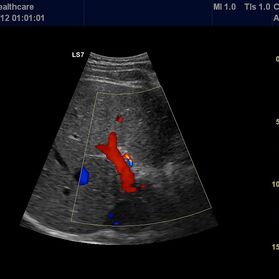

Die Ultraschall-Untersuchung ist mit Recht eine der wichtigsten und häufigsten Untersuchungsmethoden. Der Ultraschall ist ein bildgebendes Verfahren. Er erlaubt, von außen in den menschlichen Körper hinein zu sehen. So können die inneren Organe enorm detailreich und aussagekräftig untersucht werden. Vor allem die Weichteile wie Leber, Bauchspeicheldrüse, Galle, Niere oder Milz, die beim Röntgen nur schlecht zu sehen sind, können ausgezeichnet dargestellt werden.

Die Ultraschalluntersuchung ist ein sehr schnelles und leistungsstarkes Diagnoseverfahren. Dabei kann der Arzt Abläufe im Körper in Echtzeit sehen! Er hat keine Momentaufnahme vor sich, wie auf den Bildern des Röntgens oder der Computertomographie, sondern ein bewegtes Bild. Um zum Beispiel die Darmbeweglichkeit oder Organdurchblutung darzustellen, ein großer Vorteil. Da Sie als Patient dabei nicht in einer Röhre liegen, sondern ihr behandelnder Arzt neben Ihnen ist, kann ganz gezielt untersucht werden; dabei Beschwerdepunkte gezeigt, Befunde direkt erläutert und das weitere Vorgehen abgesprochen werden.